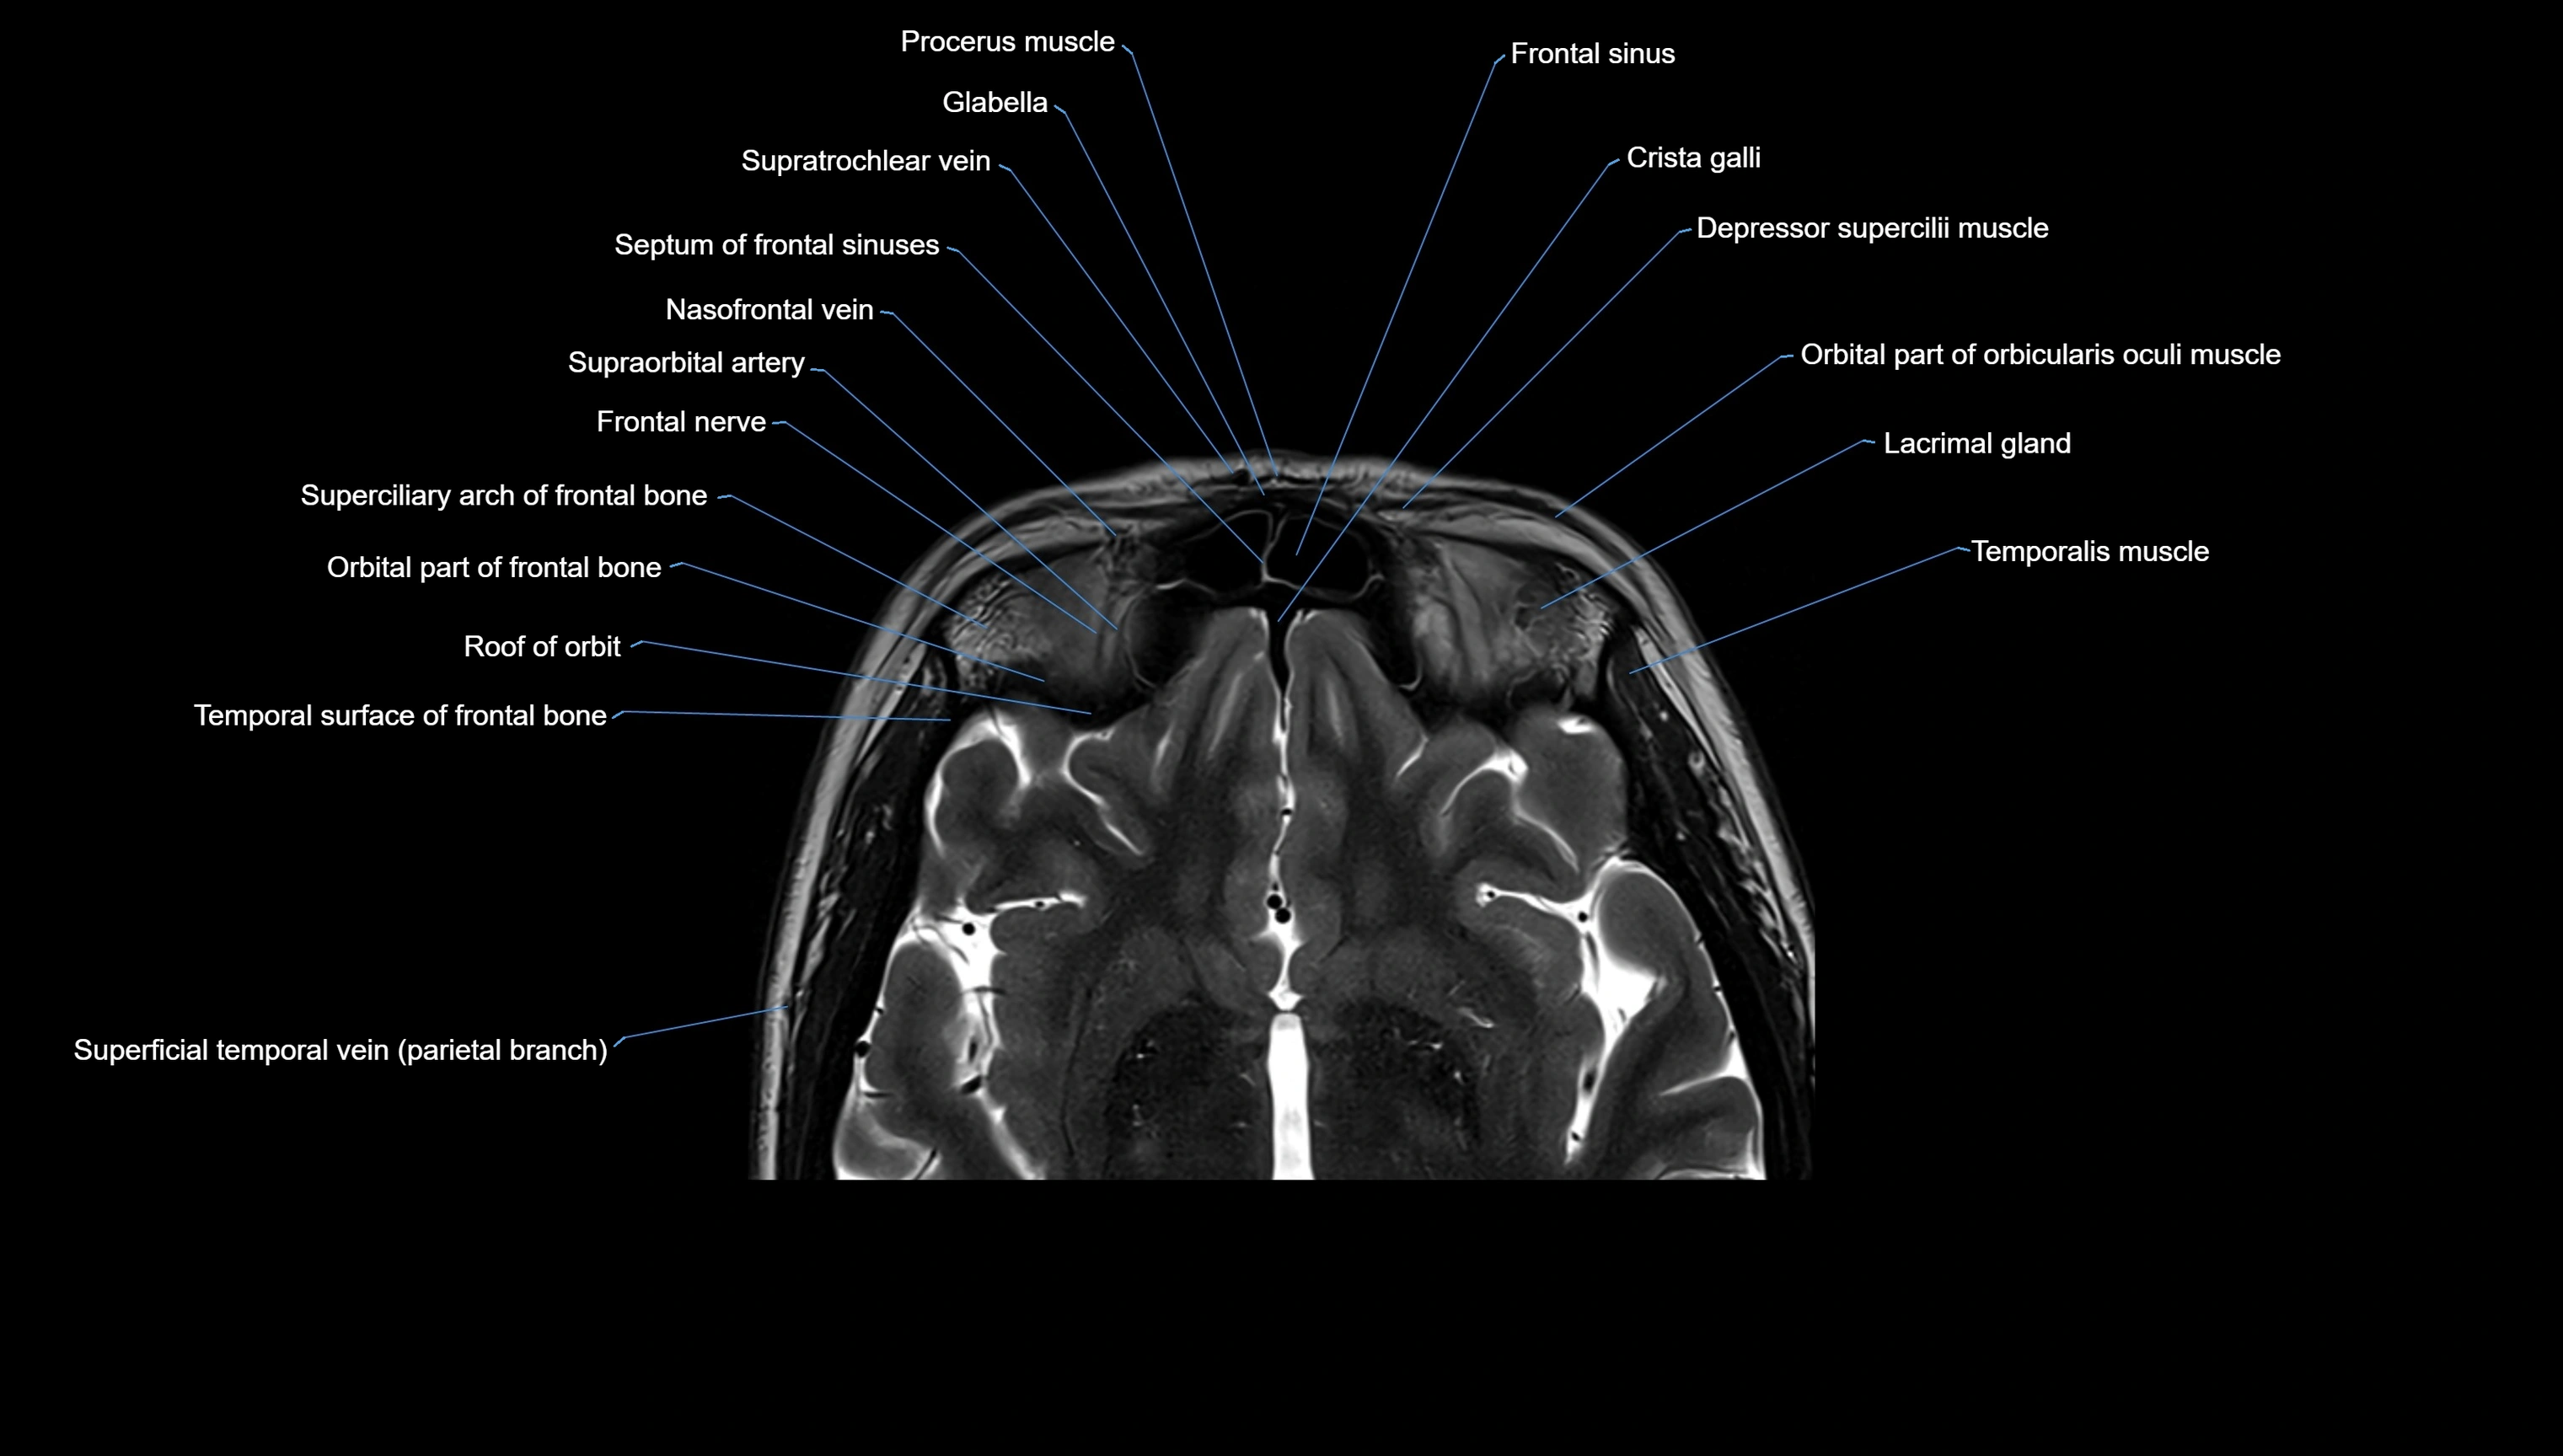

MRI images